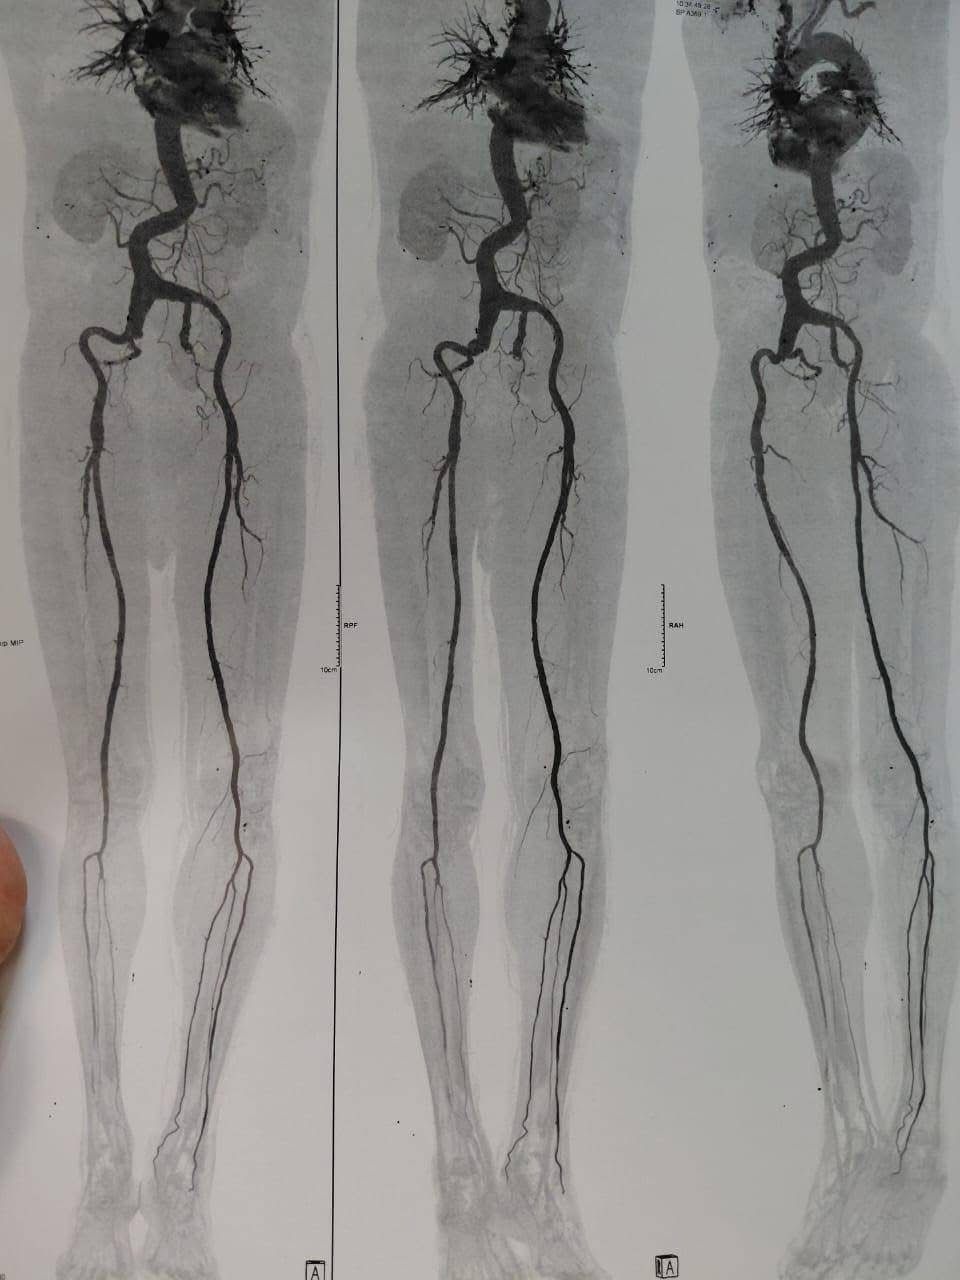

نجح فريق جراحة الأوعية الدموية بمستشفى كفر الشيخ الجامعي في إجراء عملية جراحية متقدمة لإصلاح تمدد ضخم بالشريان الأورطي البطني والشرايين الحرقفية بالحوض باستخدام شريان صناعي متفرع، وذلك لأول مرة داخل محافظة كفر الشيخ.

والجدير بالذكر، أن العملية التي أُجريت بنجاح هي من العمليات الدقيقة والمعقدة جدًا، والمعروفة طبيًا باسم

Aorto bi-iliac bypass with re-anastmosis of IIA using a pantaloon graft for a huge AORTOILIAC aneurysm،

وقد خرجت الحالة بحمد الله بسلام وصحة تامة بعد أن تم التعامل مع التمدد الضخم بدقة وكفاءة عالية.